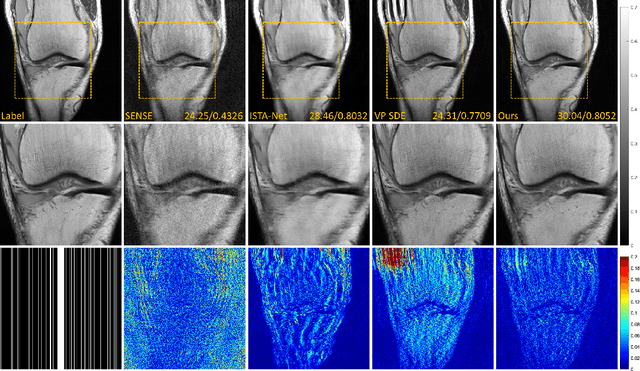

Abstract:Denoising diffusion probabilistic models (DDPMs) have been shown to have superior performances in MRI reconstruction. From the perspective of continuous stochastic differential equations (SDEs), the reverse process of DDPM can be seen as maximizing the energy of the reconstructed MR image, leading to SDE sequence divergence. For this reason, a modified high-frequency DDPM model is proposed for MRI reconstruction. From its continuous SDE viewpoint, termed high-frequency space SDE (HFS-SDE), the energy concentrated low-frequency part of the MR image is no longer amplified, and the diffusion process focuses more on acquiring high-frequency prior information. It not only improves the stability of the diffusion model but also provides the possibility of better recovery of high-frequency details. Experiments on the publicly fastMRI dataset show that our proposed HFS-SDE outperforms the DDPM-driven VP-SDE, supervised deep learning methods and traditional parallel imaging methods in terms of stability and reconstruction accuracy.